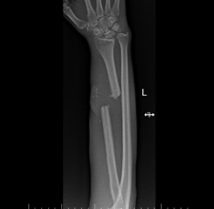

Escherichia hermannii: A Rare Pathogen in Implant-Associated Infection Following a Type III C Open Distal Radius Fracture – A Case Report

M Jyothiprasanth , C R Jithin , S Venkatesh Kumar , Rohini Venkatesh , T P Ajinas , Mohamed Hadi Mansoor